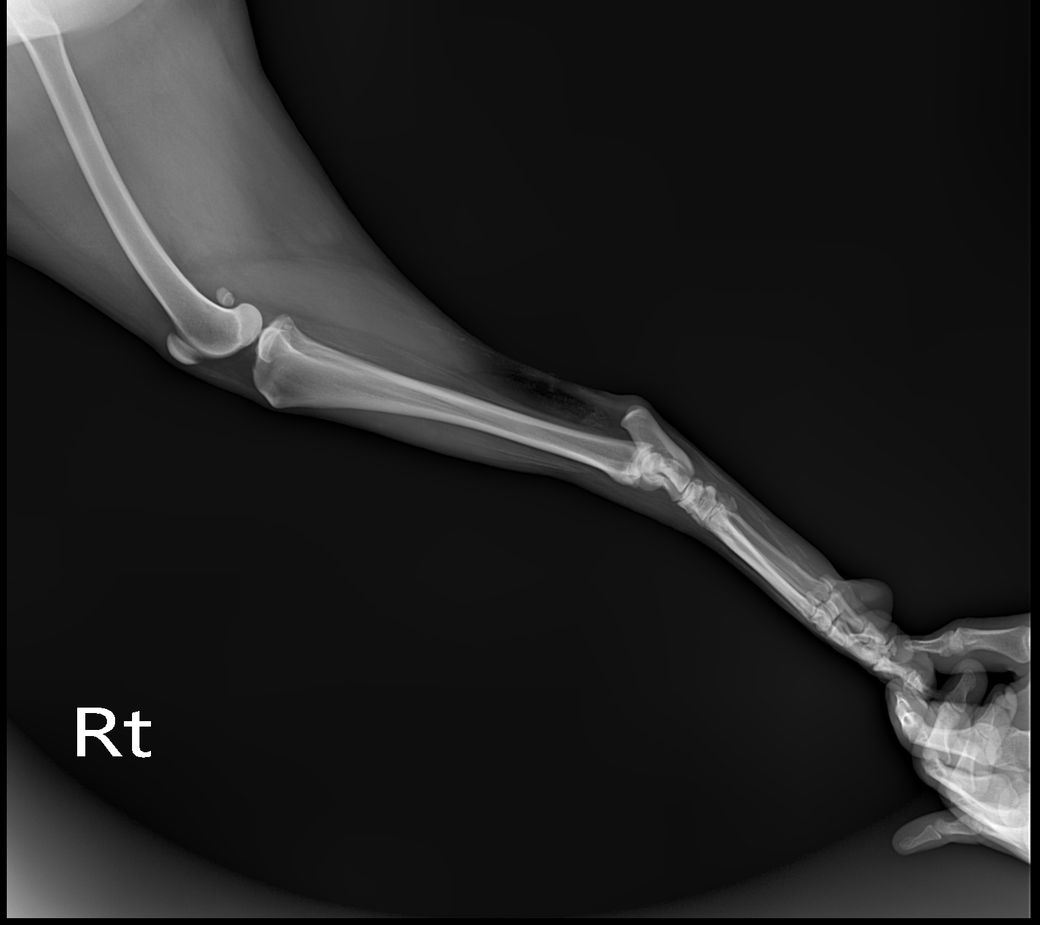

정상 발 사진

화살표로 표시된 부분의 근육 혹은 인대의 석회화 양상이 매우 뚜렷한 양상을 보이고 있고, 이는 양측 후지 모두에서 관찰되는 바 대사성 질환이나 전신성 질환이 있을 가능성이 높고,

화살표 한 부분이 반대쪽에 비해 부종 양상이 명확하게 관찰되기 때문에 근육 및 인대의 석회화를 유발하는 질환 https://diamed.tistory.com/1023 이 원발로 있다가 충격에 의해 인대나 근육이 찢어졌을 가능성이 높다는것을 의미합니다.